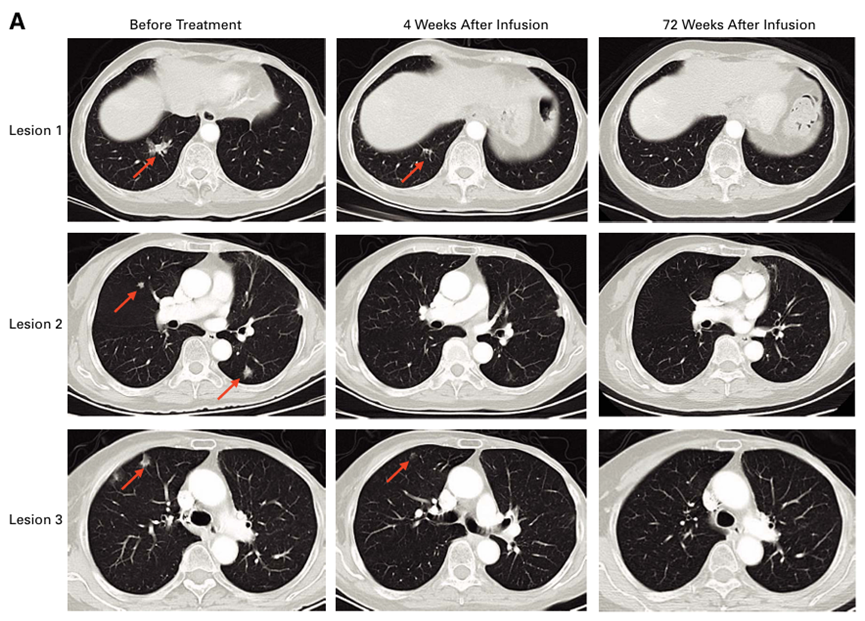

导读 Part.1 CAR-T细胞治疗晚期肝癌,90.9%的患者肿瘤缩小! 在美国临床肿瘤学会(ASCO)年会上曾公布了一项靶向GPC3得CAR-T细胞疗法临床试验结果,引起了广泛关注[1]! 这项临床研究中共入组24名患者,接受了靶向GPC3 CAR-T细胞疗法。这些患者中有83.3%(20/24)有肝外转移,而且都经过了多线肿瘤治疗方法,他们的既往治疗的中位线数为3.5,例如有23名(95.8%)患者接受了ICIs(免疫检查点抑制剂)和TKIs(酪氨酸激酶抑制剂)的治疗,但都失败了。 不过从CAR-T细胞疗法的结果中看数据是非常令人兴奋!在22名患者可进行疗效评估中,高达90.9%的患者肿瘤在CAR-T细胞治疗后缩小,总体客观有效率(ORR)为50.0%。非常值得关注的一点是,CAR-T细胞治疗疗效不仅在肝内病灶中,而且在肝外病灶中也得到了明显的效果。其中有一位患者的肿瘤病灶直接缩小了94.4%!并且从安全性方面来说,CAR-T细胞治疗安全性可控。 图:总体客观有效率(ORR)为50.0% 图源:ascopubs.org Part.2 CAR-T细胞治疗“癌王”胰腺癌,疾病控制率达到70.8%! 国际顶级肿瘤杂志Journal of Clinical Oncology(IF=45)杂志上发表的这项研究就为胰腺癌患者带来生存的希望:研究者汇总分析了两项关于CAR-T细胞治疗难治性转移性胰腺癌患者的安全性和有效性,结果显示疾病控制率达到70.8%! 两项研究共纳入24例胰腺癌患者,中位年龄为56岁(范围30-74岁)。所有患者都存在广泛转移的情况,其中一半的患者(12例)存在肝转移,33.3%患者(8例)存在腹膜转移;79.2%患者之前接受过至少两线治疗。 中位随访时间为17.3个月,有4例达到了部分缓解(PR),总体有效率(ORR)为16.7%,疾病控制率(DCR)为70.8%,临床获益率(CR/PR+SD≥4个月)为37.5%,12例患者中发现肿瘤靶病灶缩小。17例(70.8%)患者的CA19-9水平降低了至少30%。并且CAR-T细胞疗法获得的缓解是持久的,可以看到中位缓解持续时间(mDoR)为9.5个月,12个月的DoR率能够为50%。尽管该队列中的大多数患者接受了超过2线治疗,但CAR-T细胞治疗显示出良好的总生存数据。总体上,CAR-T细胞疗法在胰腺癌患者中显示出可接受的安全性,没有观察到预设的剂量限制性毒性。 其中,有一位74岁女性患者,CAR-T细胞治疗后4周的首次评估中被判定为部分缓解(PR),后续随访中发现肺转移灶进一步消失并达到完全缓解(CR)。 图:CAR-T细胞疗法治疗后红色箭头的肺部转移灶消失 图源:ascopubs.org

[1] Qi Zhang, Qihan Fu, Wanyue Cao, et al. (2024). Phase I study of C-CAR031, a GPC3-spe cific TGFbRIIDN armored autologous CAR-T, in patients with advanced hepatocellular carcinoma (HCC). J. Clin. Oncol. 42, 4019. https://doi. org/10.1200/JCO.2024.42.16_suppl.4019.

[2] Changsong Qi , Panpan Zhang , Chang Liu , et al.Safety and Efficacy of CT041 in Patients With Refractory Metastatic Pancreatic Cancer: A Pooled Analysis of Two Early-Phase Trials. J Clin Oncol. 2024 Jul 20;42(21):2565-2577. doi: 10.1200/JCO.23.02314. Epub 2024 May 24.